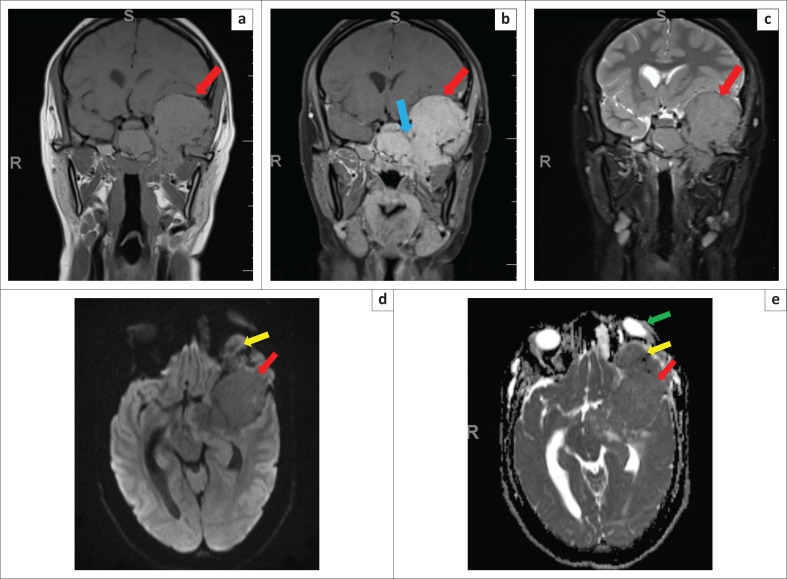

Plasma cell neoplasia has a wide presentation of disease (localised or systemic) according to the International Myeloma Working Group. Radiological imaging identifies plasmacytomas as solitary lesions or part of multiple myeloma. We present a rare case of a 21-year-old female who presented with a skull-base tumour.

Contribution: A head and neck plasmacytoma with further lytic bone lesions was confirmed on imaging. This article presents and discusses the clinical, CT, MRI, positron emission tomography (PET)-CT, histology and laboratory findings.